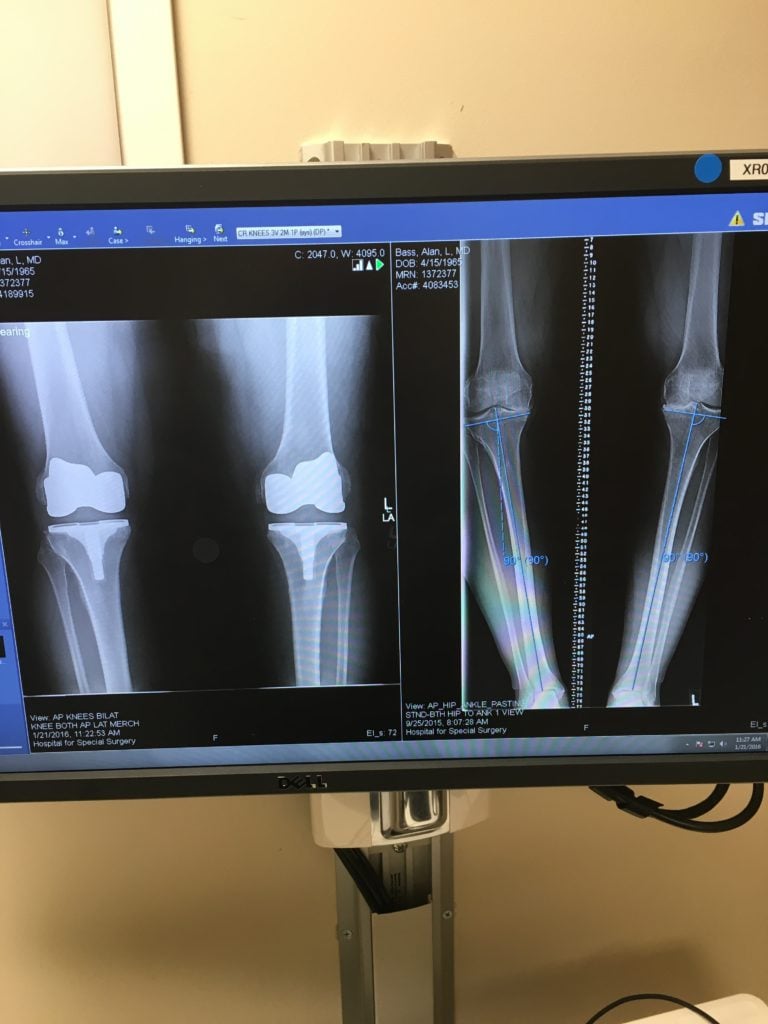

Dr. Caroline Andrew came highly recommended by Dr. Steve Haas, also from HSS. He successfully performed my bilateral knee replacement surgery 20 years earlier. I met with Dr. Andrew in January of 2019. She was attentive. She listened to my long story. She cared. She explained several options. I felt hopeful. She reached out to my team of doctors and discussed the medications I was currently on. She challenged that some medications which promote weight gain could be replaced with more suitable medications which do not. We had a plan. She connected me with Sue Xiao Yu, a nutritionist and together we embarked on a weight loss journey. We met monthly to discuss my progress and to tweak the plan accordingly. By the end of 2019 I lost almost 80 pounds. To date I've lost about 100 pounds and although COVID-19 has affected everyone's lives, I've somehow been able to keep the weight off.